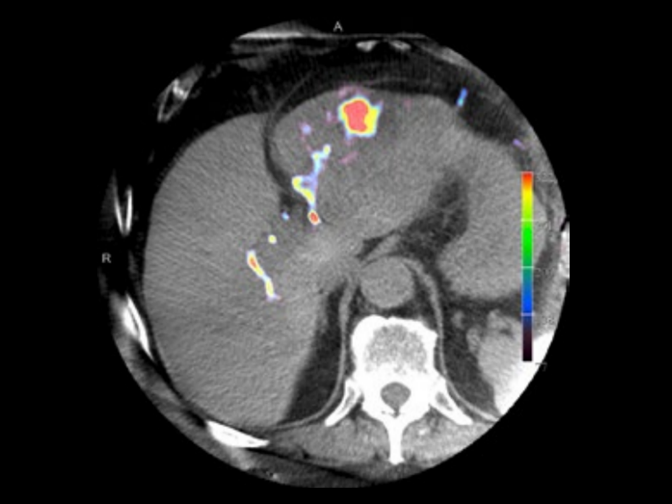

Courtesy: Prof. Vogl, Dept. of Diagnostic and Interventional Radiology, University of Frankfurt, Germany

Blood volume map overlaid on native syngo DynaCT images provided by syngo DynaPBV Body.